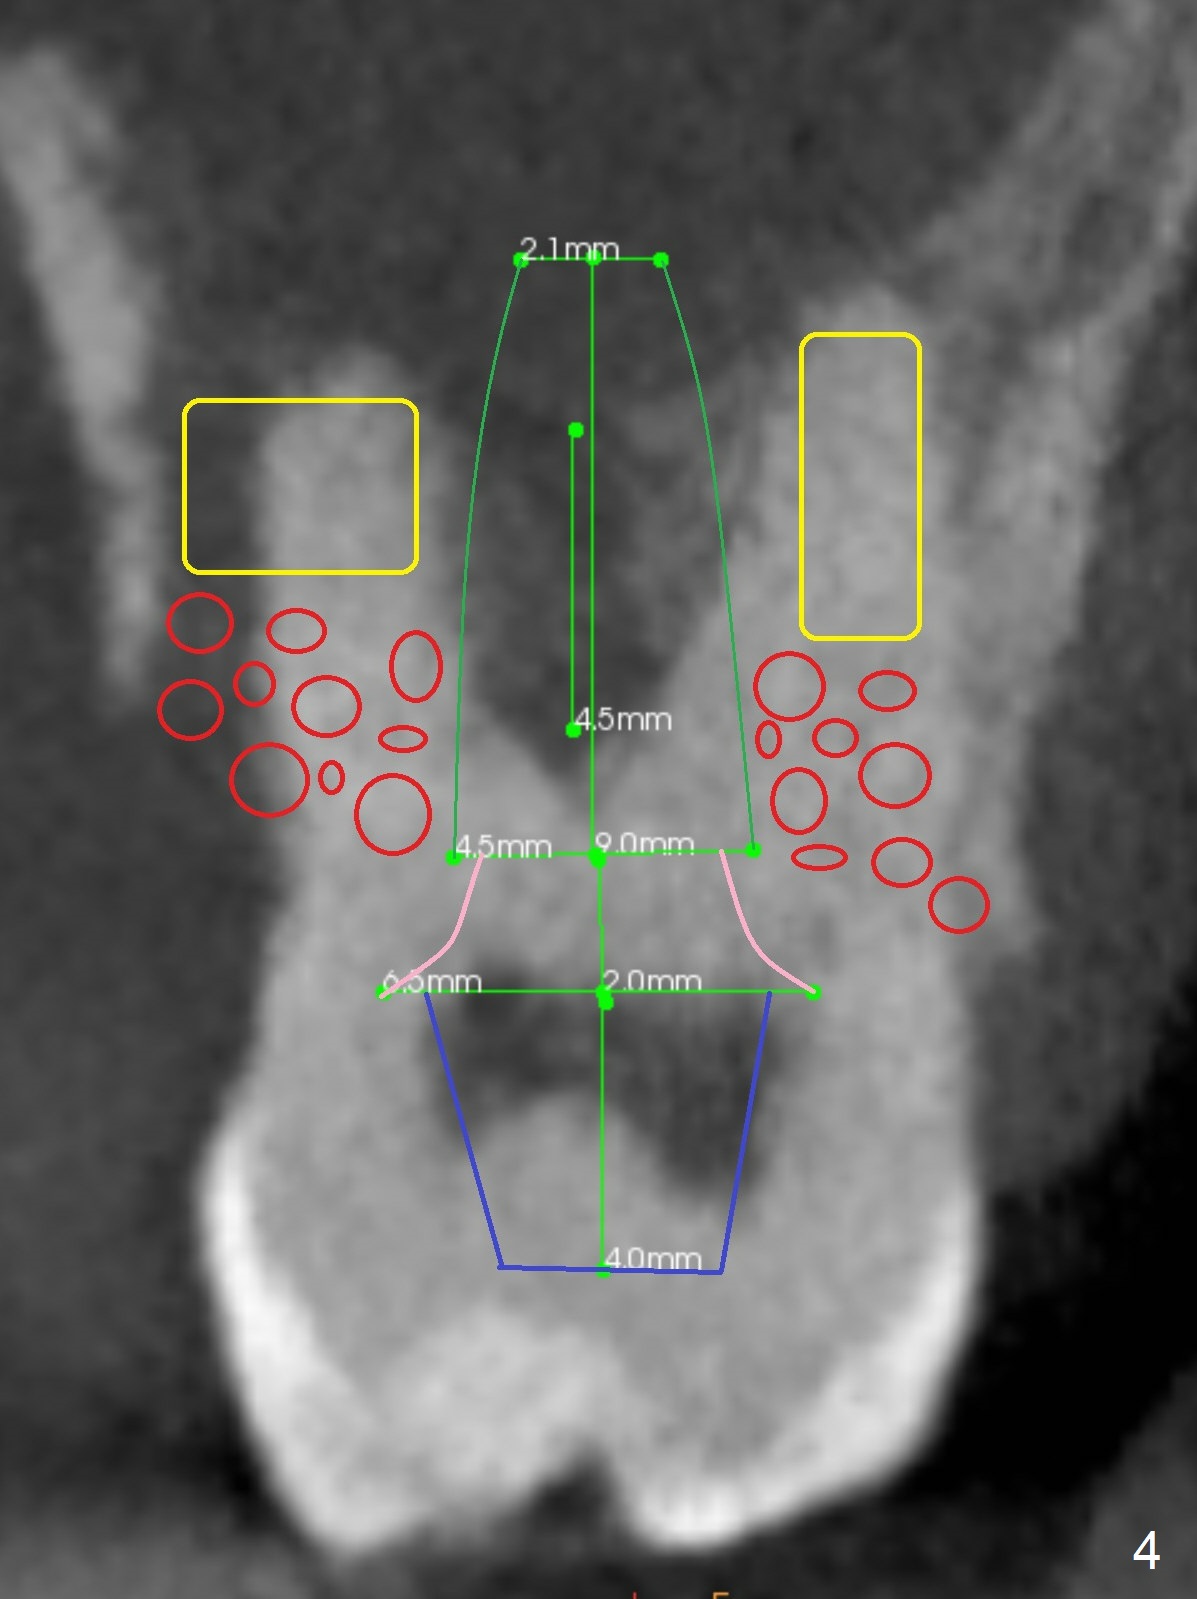

A 40-year-old man develops an abscess around the buccal roots of the tooth #15 several years after extraction of the symptomatic tooth #16. The pattern of infection is similar to that between #17 and 18. There is severe bone loss (Fig.1 *) around the fused buccal roots (Fig.2). It appears that an immediate implant (green) placed in the septum (Fig.4) has better position and angulation for restoration than the one placed in the palatal socket (Fig.3). Pink: cuff of abutment (blue); yellow: Osteogen Plug; red: bone graft.